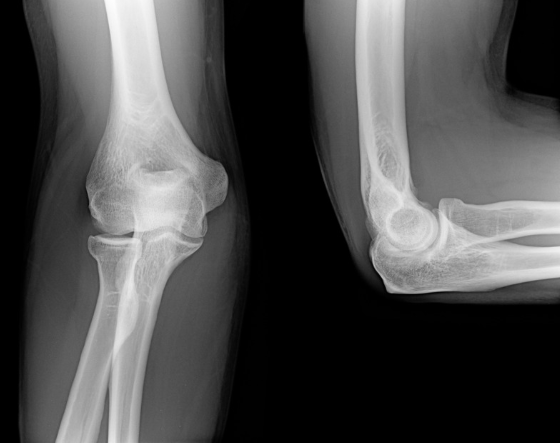

テニス肘・上腕骨外側上顆炎の診断

診察では肘のスジの付着部を軽く押したり、手首を反らして肘の痛みが生じるかを確認します。またレントゲンで肘の変形がないかを確認し、エコーでスジが腫れてたり痛んでいたら(下の図)、診断が確定します。